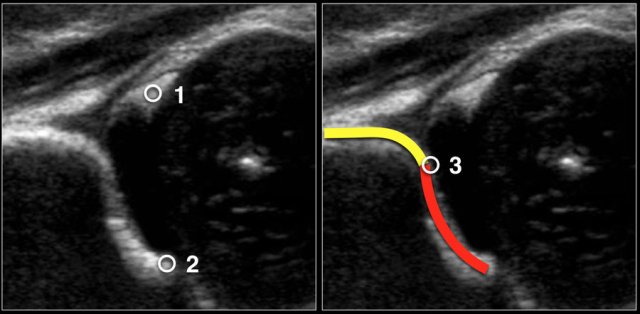

First three points of interest need to be indentified in the image:

1. Centre of labrum

2. Lower limb of the iliac bone (=Undersurface of the medial border of the acetabulum where the iliac bone meets the triradiate cartilage)

3. Bony rim of acetabulum. When the bony rim is angular this point is easily recognized. When rounded this point is defined as the point where the concavity of the bony acetabular roof changes into the convexity of the ilium

When you perform the ultrasound examination, make sure that these three points can be identified on the image.